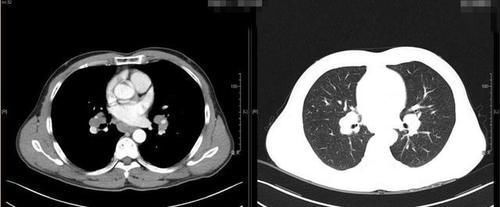

准确的说肺结节其实是影像科医师对于胸部CT显示的局灶性病灶的一种描述。我们通常把胸部CT上直径小于3cm肺部病灶统称为肺结节。

研究表明,绝大部分肺结节都是良性的。肺结节的体积越小,良性程度越高,恶性几率越低。

体积非常小的肺结节往往缺乏典型的临床症状,或者说干脆就没什么不舒服的地方。很多朋友都是在单位组织健康体检的时候偶然发现的。对于无症状、体积又非常小的肺结节,不建议盲目的手术切除。可以选择定期复查、随诊。动态行胸部CT检查,观察肺结节的变化情况。结节越小,随访周期越长。结节体积越大,随访间隔时间应该越短。